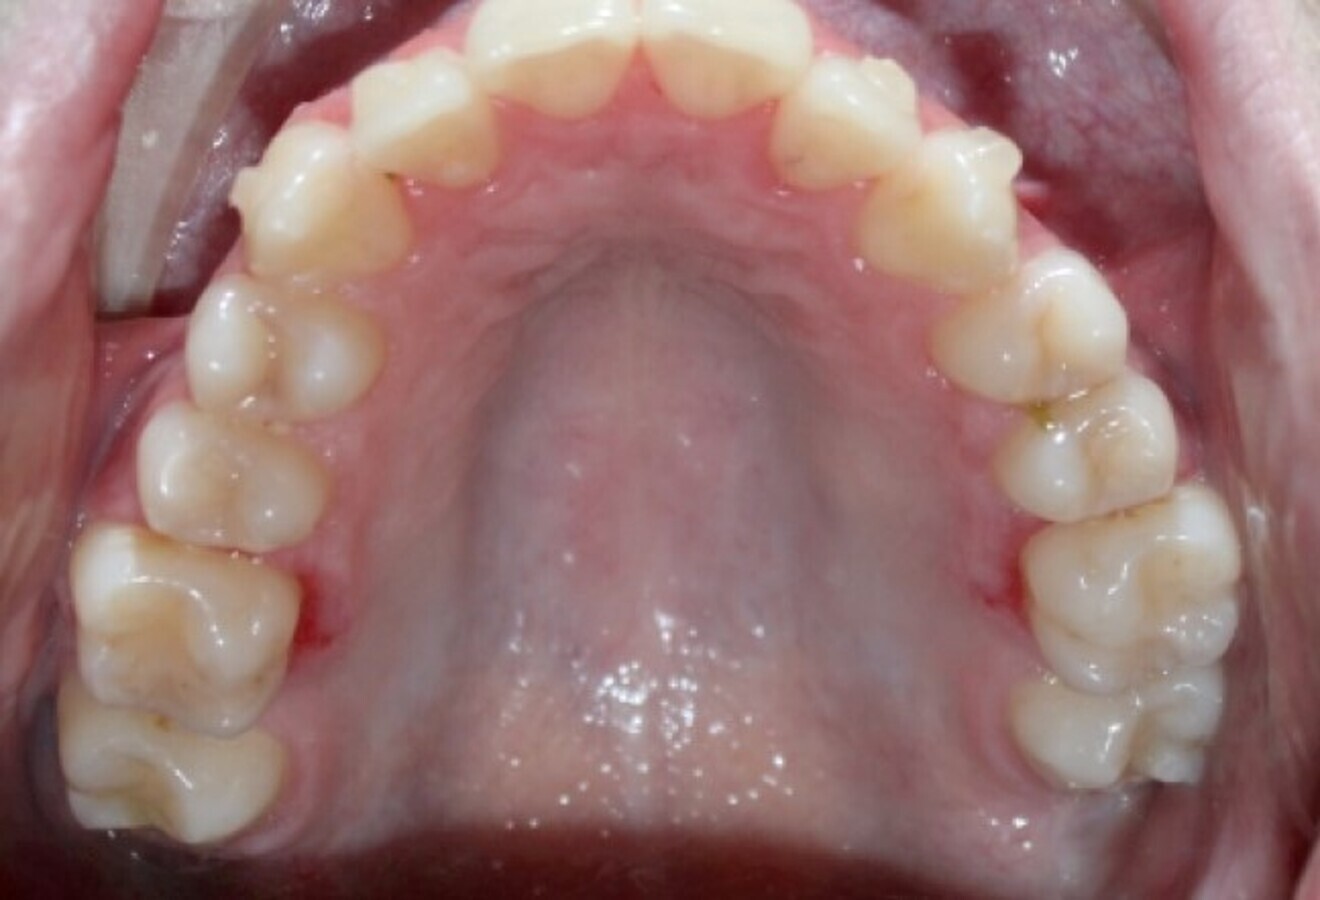

Fig. 19a: After six months of the Carriere Motion appliance and aligners. (a) Lateral view. (b) Occlusal view.

Fig. 19b: After six months of the Carriere Motion appliance and aligners. (a) Lateral view. (b) Occlusal view.